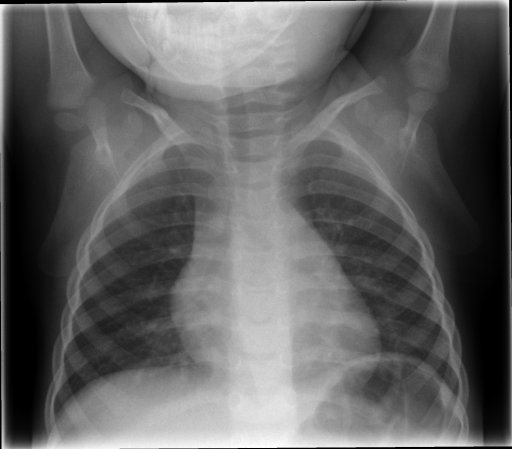

The IRMA dataset, supplied for the imageCLEF organization, had annotated codes were similar to domain expert knowledge [9, 12, 13, 14]. This database has been used by many researchers and is comprised of preset test and training portions, which enable direct comparisons of metrics. The IRMA codes (manually created by several clinicians) contains information on technical, biological and diagnostic traits of the image in a structured manner: TTTT-DDD-AAA-BBB. Each section is hierarchical meaning there is a least significant bit and most significant digit (Table 1). Sample IRMA images are depicted in Fig. 1.